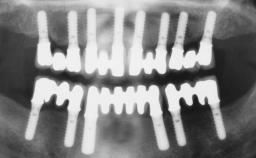

A fully edentulous 65-year-old woman was referred to our clinic for esthetic and functional dental rehabilitation. The patient presented with inadequate complete maxillary and mandibular prostheses, insufficient vertical dimension, and extensive tooth wear. The clinical examination and anamnesis showed no local or systemic contraindications, no signs or symptoms of bruxism, and an absence of smoking habits. The treatment proposed was implant placement in the mandibular interforaminal area and immediate loading with a fixed definitive prosthesis. A removable mucosa-supported complete prosthesis was indicated for the upper jaw, since its bone structure offered satisfactory retention and the financial condition of the patient disfavored a full-mouth implant-supported rehabilitation.